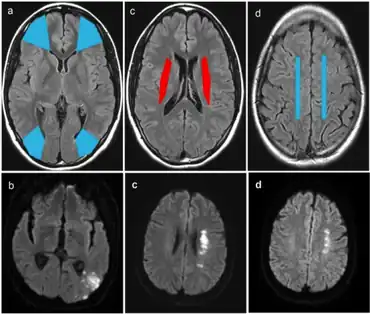

A watershed stroke is defined as a brain ischemia that is localized to the vulnerable border zones between the tissues supplied by the anterior, posterior and middle cerebral arteries. [1] The actual blood stream blockage/restriction site can be located far away from the infarcts. Watershed locations are those border-zone regions in the brain supplied by the major cerebral arteries where blood supply is decreased. Watershed strokes are a concern because they comprise approximately 10% of all ischemic stroke cases.[2] The watershed zones themselves are particularly susceptible to infarction from global ischemia as the distal nature of the vasculature predisposes these areas to be most sensitive to profound hypoperfusion.[1]

Watershed strokes are localized to two primary regions of the brain, and are termed cortical watersheds (CWS) and internal watersheds (IWS).[3] Patients with many different cardiovascular diseases have a higher likelihood of experiencing a blood clot or loss of blood flow in border-zone regions of the brain. The resulting symptoms differ based on the affected area of the brain. A CT scan and MRI are used for diagnosis, and afterward several treatment options are available, including the removal of atherosclerotic plaque and a physical widening of the clogged blood vessel. Long-term care is focused around three areas: rehabilitative therapy, surgical interventions, and prevention of future watershed strokes. Going forward, research to combat watershed strokes is focusing on various topics, such as stem cell research.

These events are localized to two primary regions of the brain:

- Cortical watershed strokes (CWS), or outer brain infarcts, are located between the cortical territories of the anterior cerebral artery (ACA), middle cerebral artery (MCA), and posterior cerebral artery (PCA).[3]

- Internal watershed strokes (IWS), or subcortical brain infarcts, are located in the white matter along and slightly above the lateral ventricle, between the deep and the superficial arterial systems of the MCA, or between the superficial systems of the MCA and ACA.[3]